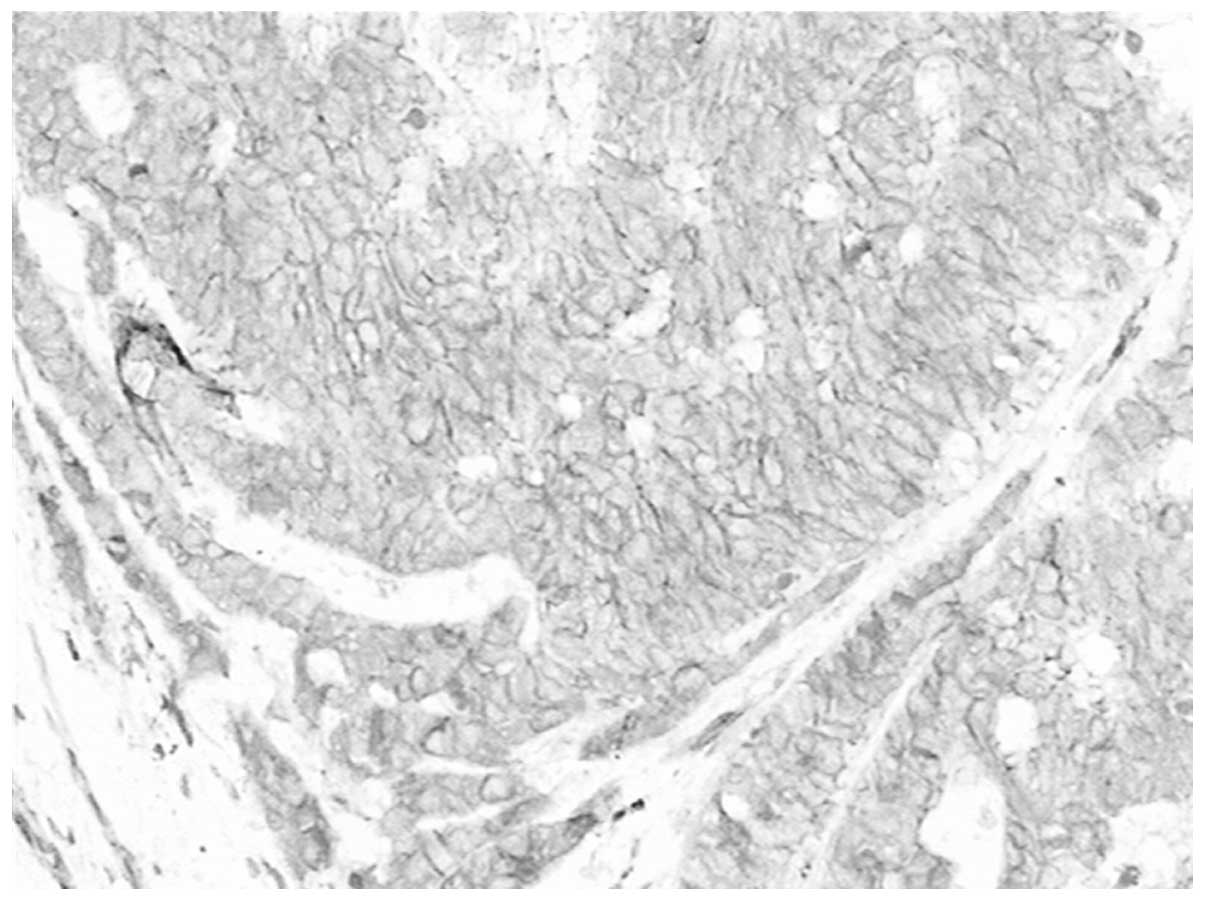

Correlation of CD146 expression and clinicopathological characteristics in esophageal squamous cell carcinoma

CD146, a cell adhesion molecule, is found in normal and tumor tissues. The level of its expression has been found to directly correlate with tumor progression and metastatic potential. The objective of this study was to investigate the expression of CD146 in esophageal squamous cell carcinoma (ESCC) and its correlation with clinicopathological parameters. Tumor specimens were collected from 63 patients with ESCC who underwent complete resection. We analyzed the CD146 expression levels in ESCC by immunohistochemistry. The expression of CD146 was detected and it was observed to correlate with clinicopathological parameters. Sixty‑three cases of normal squamous mucosa were included for comparison. CD146 expression was identified in 46.0% (29/63) of the ESCC samples, and no positive (weak to moderate or moderate to strong) expression was found in the normal squamous epithelium samples (χ2=27.248; P<0.0001). CD146 expression was associated with lymph node metastasis (χ2=5.117; P=0.024) and advanced clinical stage (χ2=4.661; P=0.031). CD146 expression was one of the significant predictors of survival (hazard ratio, 2.838; 95% confidence interval 1.102‑7.305). The overexpression of the CD146 gene was one of the important phenotypes and characteristics in ESCC carcinomatous change. We found that CD146 expression was associated with lymph node metastasis and advanced clinical stage, and was an indicator of poor prognosis in ESCC patients. CD146 may prove to be an important tumor marker for the individualized treatment for ESCC.